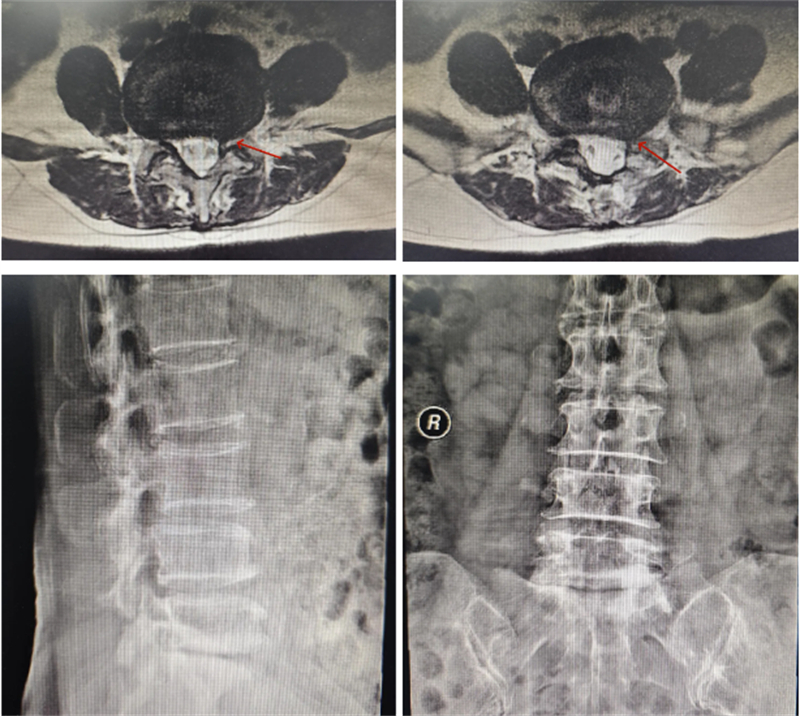

術(shù)前影像

為了徹底解決這一頑疾,許女士最終決定來到柳州市人民醫(yī)院接受治療。入院后,經(jīng)過詳細(xì)的影像學(xué)檢查和臨床評(píng)估,確診其患有嚴(yán)重的腰椎管狹窄癥,神經(jīng)受壓情況較為明顯。由于患者存在明顯的腰椎骨質(zhì)增生,正常的解剖標(biāo)志部分消失,使得手術(shù)難度大大增加。在這種情況下,如何確保置釘?shù)木_性和對神經(jīng)的有效減壓成為了手術(shù)成敗的關(guān)鍵所在。